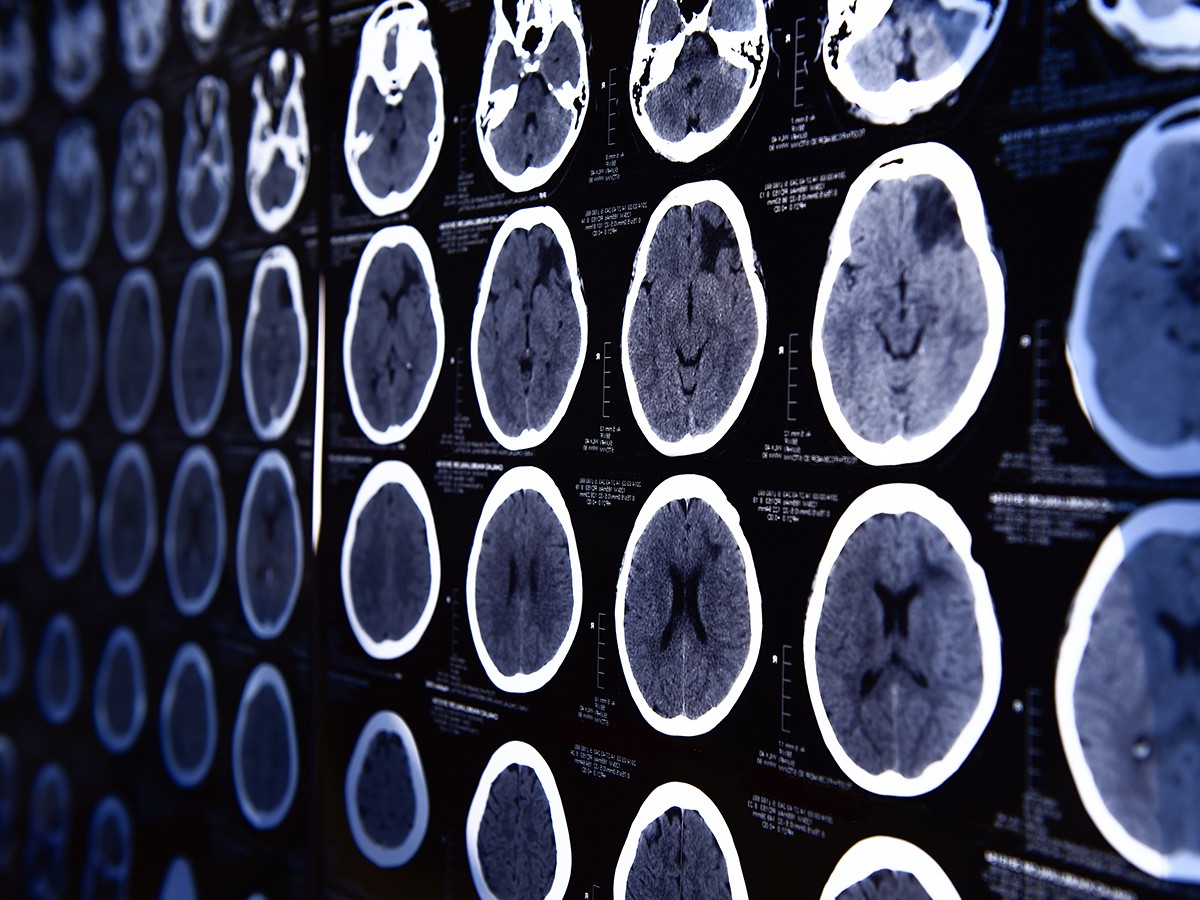

Although a variety of different procedures are used, four main ablative procedures have been used in OCD. The procedures can result in permanent lesions in the brain, that are irreversible.